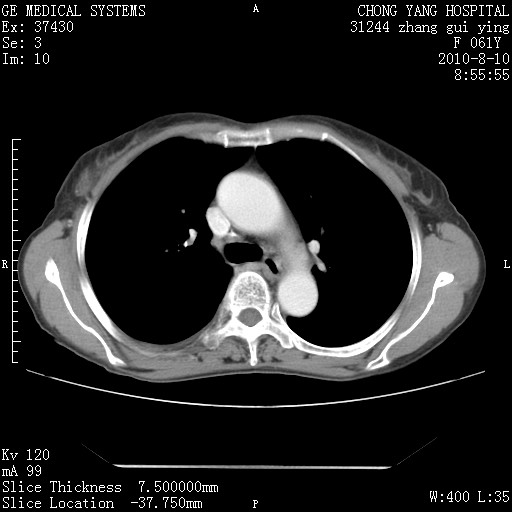

标题: CT28314:F61Y胸部增强,发热咳嗽一周入院,后面的为一周前平 [打印本页]

标题: CT28314:F61Y胸部增强,发热咳嗽一周入院,后面的为一周前平

1、支持考虑右侧中央型肺癌伴右肺中叶节段性不张及下叶支气管黏液痰栓    2、左肺上叶舌段感染。

支持3楼意见,还要考虑:纵隔及肺门淋巴结转移、右侧少量胸腔积液。

确切的说:1:右肺下叶中心型肺癌侵及中叶支气管并中叶不张,纵膈淋巴结转移。2:左肺舌叶炎症。3:右侧胸腔少量积液

块影平扫32hu,动静脉期62-70hu.

1:右肺下叶中心型肺癌侵及中叶支气管并中叶不张,纵膈淋巴结转移。2:左肺舌叶炎症。3:右侧胸腔少量积液。支持!

右肺下叶中心型肺癌侵及中叶支气管并中叶不张,纵膈淋巴结转移。2:左肺舌叶炎症。3:右侧胸腔少量积液